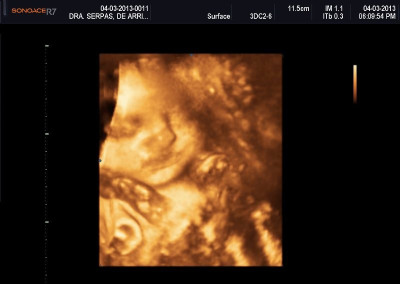

Varias ultrasonografías en 2D y 3D

Envíado por Dr. Nelson Menjívar Sarco